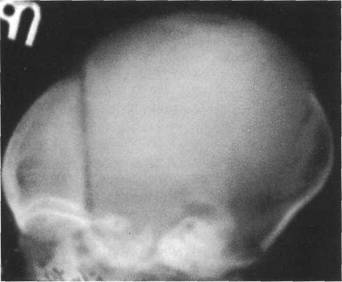

стояния теменных костей по сравнению с чешуей лобной и затылочной костей, а также на-ползания теменных костей на лобную и затылочную. Это отчетлив 121h711b о видно на боковой кра- на одном уровне. У здорового ребенка не должно быть ни их разновысокого стояния, ни,

взаимного захождения костей.